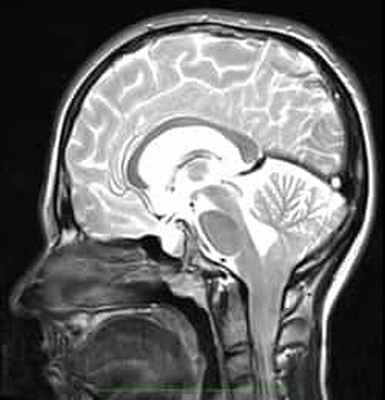

Рисунок 2.- МРТ пациента в 8 и 20 месяцев, на втором снимке можно наблюдать опущение миндалин мозжечка, которое появилось уже после первого МРТ. Huang P. “Adquired” Chiari I malformation. J. Neurosurg 1994. Это указывает на то, что, помимо наследственного и генетического фактора, существует фактор приобретенного заболевания.